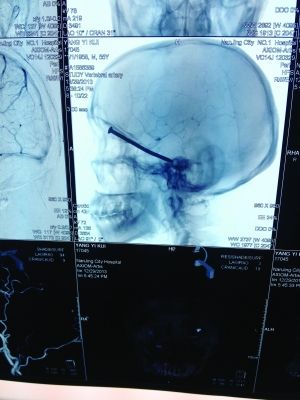

男子翻新地板遭8厘米釘從眼眶"飛"入腦中

CT投影

前幾天,市民楊先生在家翻新地板時,眼中突然飛入“異物”。去醫(yī)院檢查,發(fā)現(xiàn)這“異物”竟是一根長達8厘米的鐵釘!好在鐵釘錯開了楊先生頭部的各種大血管,醫(yī)生得以順利將其取出。

CT投影結(jié)果,把大家嚇了一跳:楊先生腦子里居然有一根長釘,從眼眶一直“伸”到了接近后腦勺的位置!鐵釘細長略帶彎曲,長達8厘米。根據(jù)推測,鐵釘應該是從上眼眶的縫隙中飛入,一直插進腦顱中,末端還有一個小小凸出的釘帽。